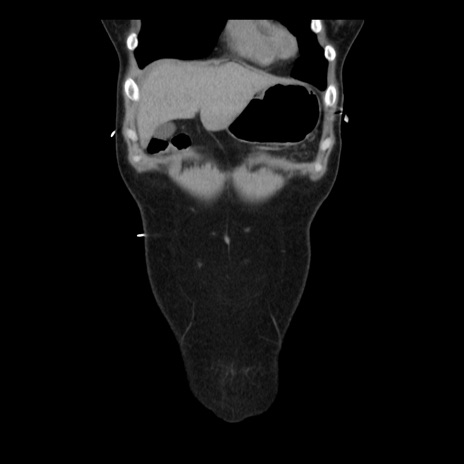

横断像

矢状断像